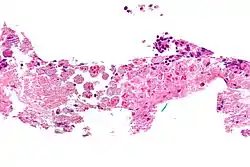

Стадія ураження товстої кишки

Назва E.histolytica напряму пов'язана з літичною дією гістолітичної амеби на тканини. Її прикріплення (адгезія) до слизової оболонки кишечника відбувається за рахунок галактозо-інгібуючого-адгезивного лектину — пептиду, який утворює пори в слизовій і, таким чином, пошкоджує кишечник. Крім цього фактору у E. histolytica знайдено безліч гемолізинів, які здатні знешкоджувати еритроцити, лейкоцити і протеази, виявлено гіалуронідазу, що сприяє проникненню амеб у тканини. При потраплянні E. histolytica до підслизового шару відбувається інтенсивне розмноження паразитів, утворюються первинні вогнища у вигляді мікроабсцесів, які розкриваються в порожнину кишечника. Таким чином, спочатку виникає виразка невеликих розмірів. При цьому амеби інтенсивно розмножуються, поширюючись по периферії виразки і проникають всередину, досягаючи м'язового шару стінки кишки. Невеликі виразки, розташовані поблизу одна від одної, можуть зливатися, в результаті утворюються великі, які мають у діаметрі декілька сантиметрів. На слизовій оболонці кишечнику при гострому амебіазі можуть одночасно виявлятися виразки різної величини і форми: від дуже маленьких, ледь помітних до гігантських. Дно виразок вкрите некротичними масами. При неускладненому перебігу амебіазу слизова оболонка між виразками без запальних змін, зберігає звичайний вигляд, що є важливим діагностичним проявом цієї хвороби. Найбільш часто виразковий процес охоплює сліпу кишку і прилеглу до неї висхідну частину товстої кишки, червоподібний відросток. На другому місці за частотою локалізації знаходяться сигмоподібна та пряма кишка. Тривалий, з хронічним перебігом, кишковий амебіаз може стати причиною утворення кіст, поліпів і амебом[14].